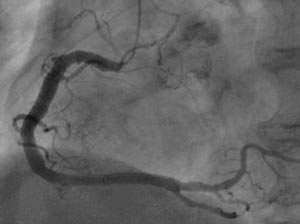

| PCI治療前と治療後 ■治療前 冠動脈造影検査で冠動脈がつまっている部分が確認できる |

![]() |

| ■治療後 PCI後。冠動脈の血流が回復している |